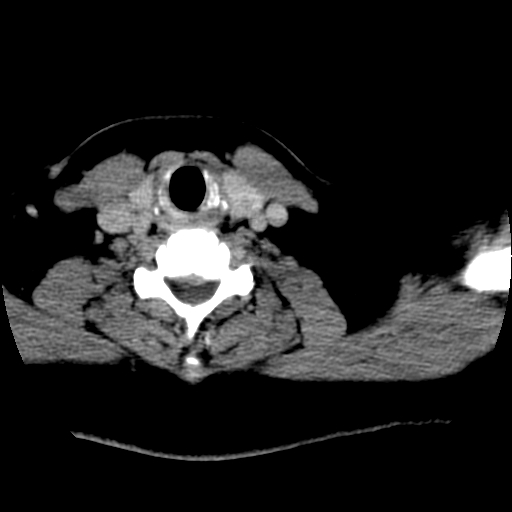

标题: CT25491:女,55岁,发现左侧甲状腺肿块一个月。 [打印本页]

标题: CT25491:女,55岁,发现左侧甲状腺肿块一个月。

女,55岁,发现左侧甲状腺肿块一个月,彩超示:甲状腺多发结节伴左叶结节液化。

考虑左侧甲状腺结节性甲状腺肿,不排除甲状腺腺瘤。